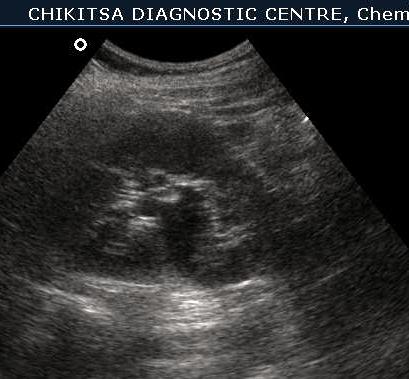

Left kidney shows hydronephrosis.